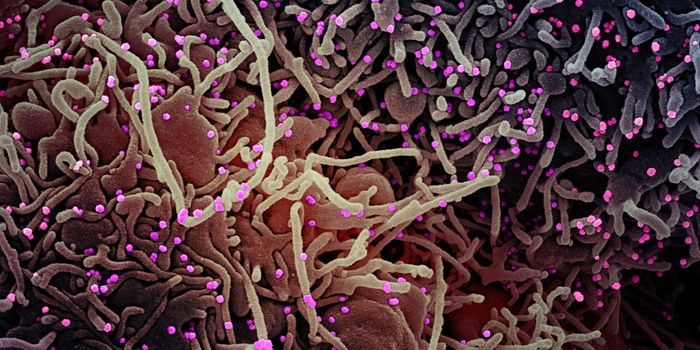

SEP 25, 2021Health & MedicineAfter a year-long study, researchers have assembled a detailed narrative about how the SARS-Cov-2 virus has spread on th ...